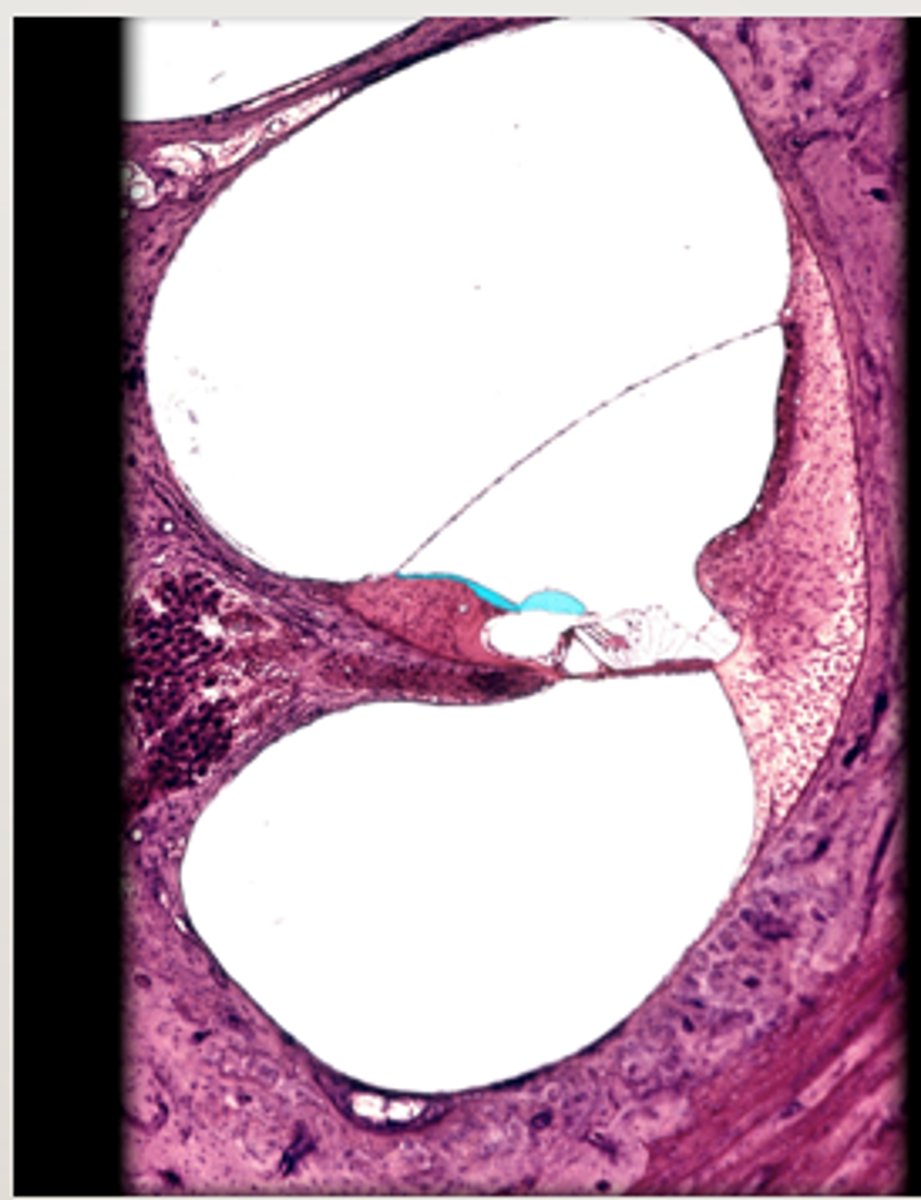

anterior chamber

posterior chamber

lens

suspensory ligament of eye

ciliary body

Iris